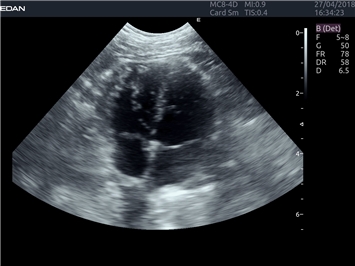

EDAN Acclarix LX4 VET

EDAN Acclarix LX4 VET представляет собой профессиональную ультразвуковую систему, специально разработанную для ветеринарных исследований. Сочетание стабильности, высокой производительности и эффективности делает эту систему идеальным выбором для современной ветеринарной практики.

• Адаптивная визуализация тканей:

• Оптимизация изображения для различных видов животных

• Улучшенная детализация структур

• Мультилучевое сложно-составное сканирование (SCI):

• Повышенная четкость изображения

• Улучшенная визуализация сложных анатомических структур